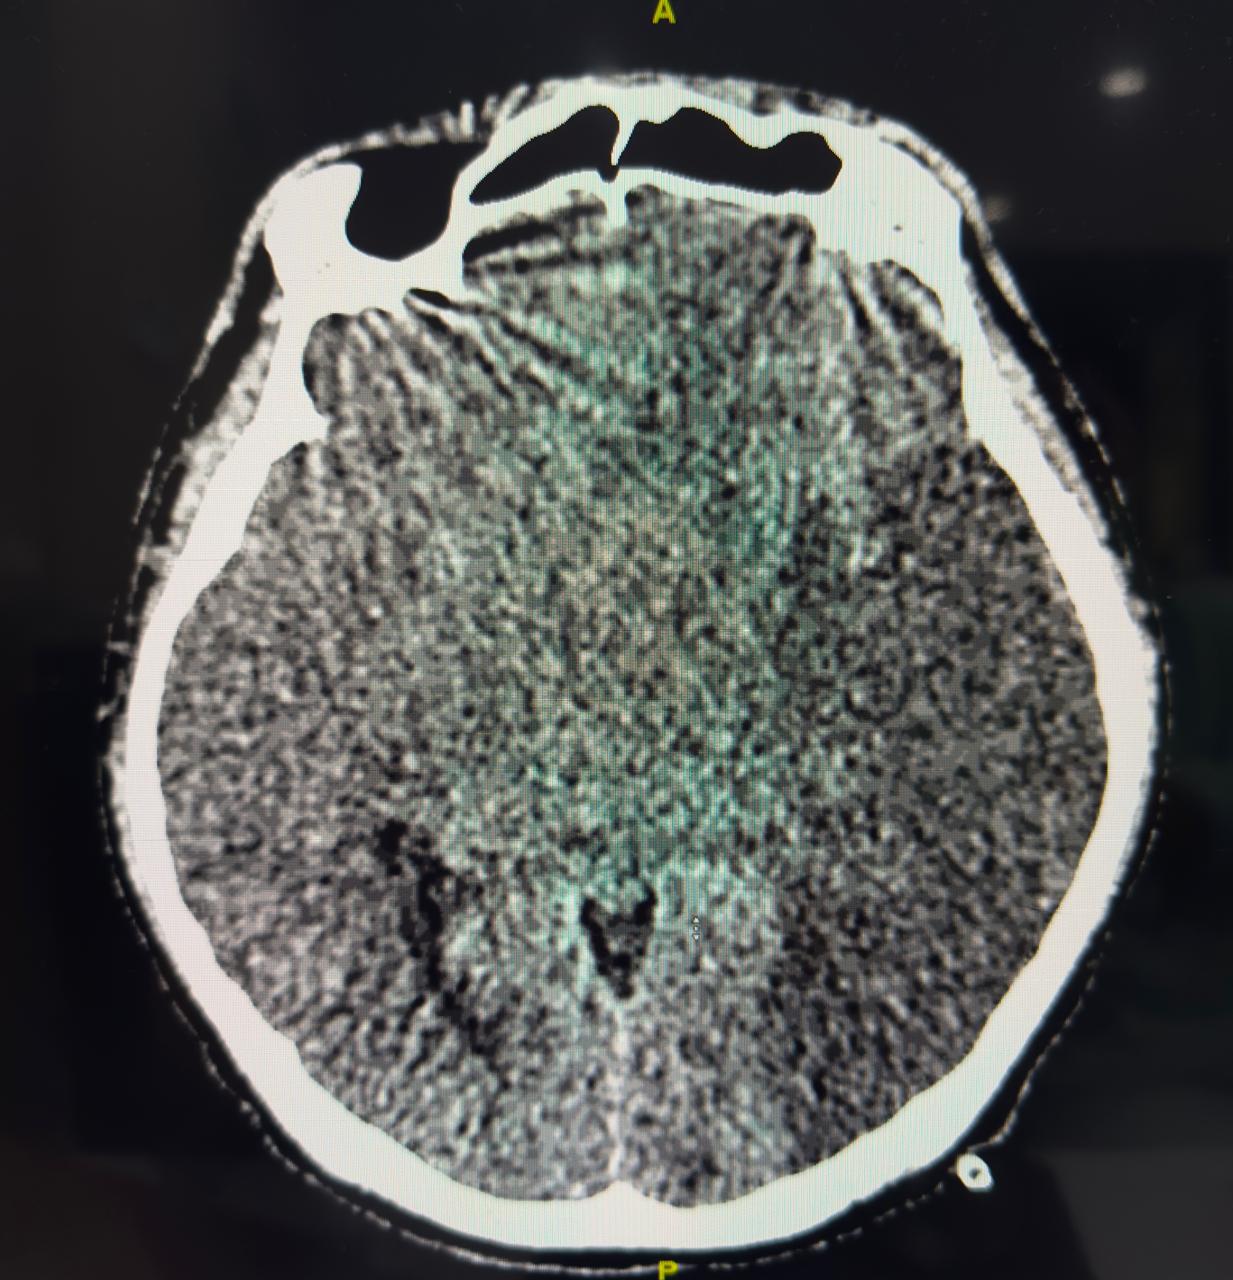

First patient develop massive ischemic stroke post PCI although patient got thrombolytic, PCI and anticoagulant and dual antiplatelet.

Both patient developed stroke periprocedural but in a paradoxical way. One with heavy thrombus burden young patient with thrombolytic, GP2B3A infusion, anticoagulation and dual antiplatelet but developed acute massive ischemic stroke and did not survive. The second patient developed acute massive haemorrhagic stroke due to sudden increase of blood pressure, despite the use of normal dose of anticoagulation, low ARC HBR score, and normal pressure during procedure. So stroke both ischemic or haemorrhagic are devastating and have high mortality, but until now there is no actual scoring system to predict only on ARC HBR to prevent bleeding periprocedural.